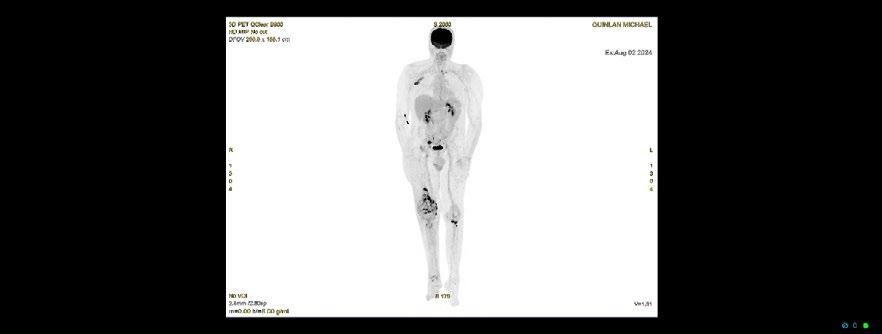

INTRODUCTION: Nuclear medicine imaging plays a pivotal role in evaluating complex prosthetic joint cases, particularly when conventional modalities are compromised by metal artifacts and nonspecific findings. This case study illustrates how the combined use of Gallium-67 scintigraphy and FDG PET imaging guided surgical intervention and evaluated disease progression with superior diagnostic sensitivity

CLINICAL PRESENTATION: A 61-year-old military veteran with a right total knee replacement presented with several months of knee swelling and severe pain. Initial evaluations including CT, bone scan, XR, ultrasound with fluid aspiration and MRI were inconclusive due to metallic artifacts and complex prosthetic fractures with adjacent oedema. The patient subsequently underwent Gallium-67 scintigraphy following an intravenous injection of 150 MBq Gallium-67 citrate, with imaging performed 48 hours later using a GE Discovery 670 system. The Gallium-67 scan demonstrated a significantly abnormal periprosthetic uptake, consistent with clinical concerns for infection. This result expediated surgical intervention and tissue biopsy of the affected area. The biopsy results revealed an extremely rare form of Diffuse Large B-cell Lymphoma involving the joint prosthesis. An FDG PET scan was then performed on a GE Omni PET system which revealed intense metabolic activity within the right knee and left knee, subcutaneous upper back activity and an FDG-avid right iliac fossa lymph node, suggesting systemic involvement. The patient underwent 6 cycles of R-CHOP and is awaiting further surgical intervention for the affected knee.

DISCUSSION: Prosthetic joint-associated lymphoma is an exceedingly rare phenomenon, with fewer than 20 cases documented in the global literature. The utility of 67Ga in lymphoma diagnosis is historically well demonstrated and this case underscores the complementary value of Gallium-67 scintigraphy and FDG PET imaging in complex prosthetic joint scenarios. While traditional imaging modalities were hampered by metal-induced artifacts and non-specific findings, nuclear medicine techniques facilitated the critical differentiation between infection and malignancy. This case also highlighted the importance of evaluating 67Ga-citrate imaging in complex clinical presentations with a comprehensive understanding of the mechanism of uptake in relevant pathologies The integrated imaging approach not only prompted surgical management but also informed systemic treatment planning, highlighting the evolving role of nuclear medicine in addressing challenging diagnostic dilemmas

Figure 1. 67Ga-citrate scan

Shimadzu Award